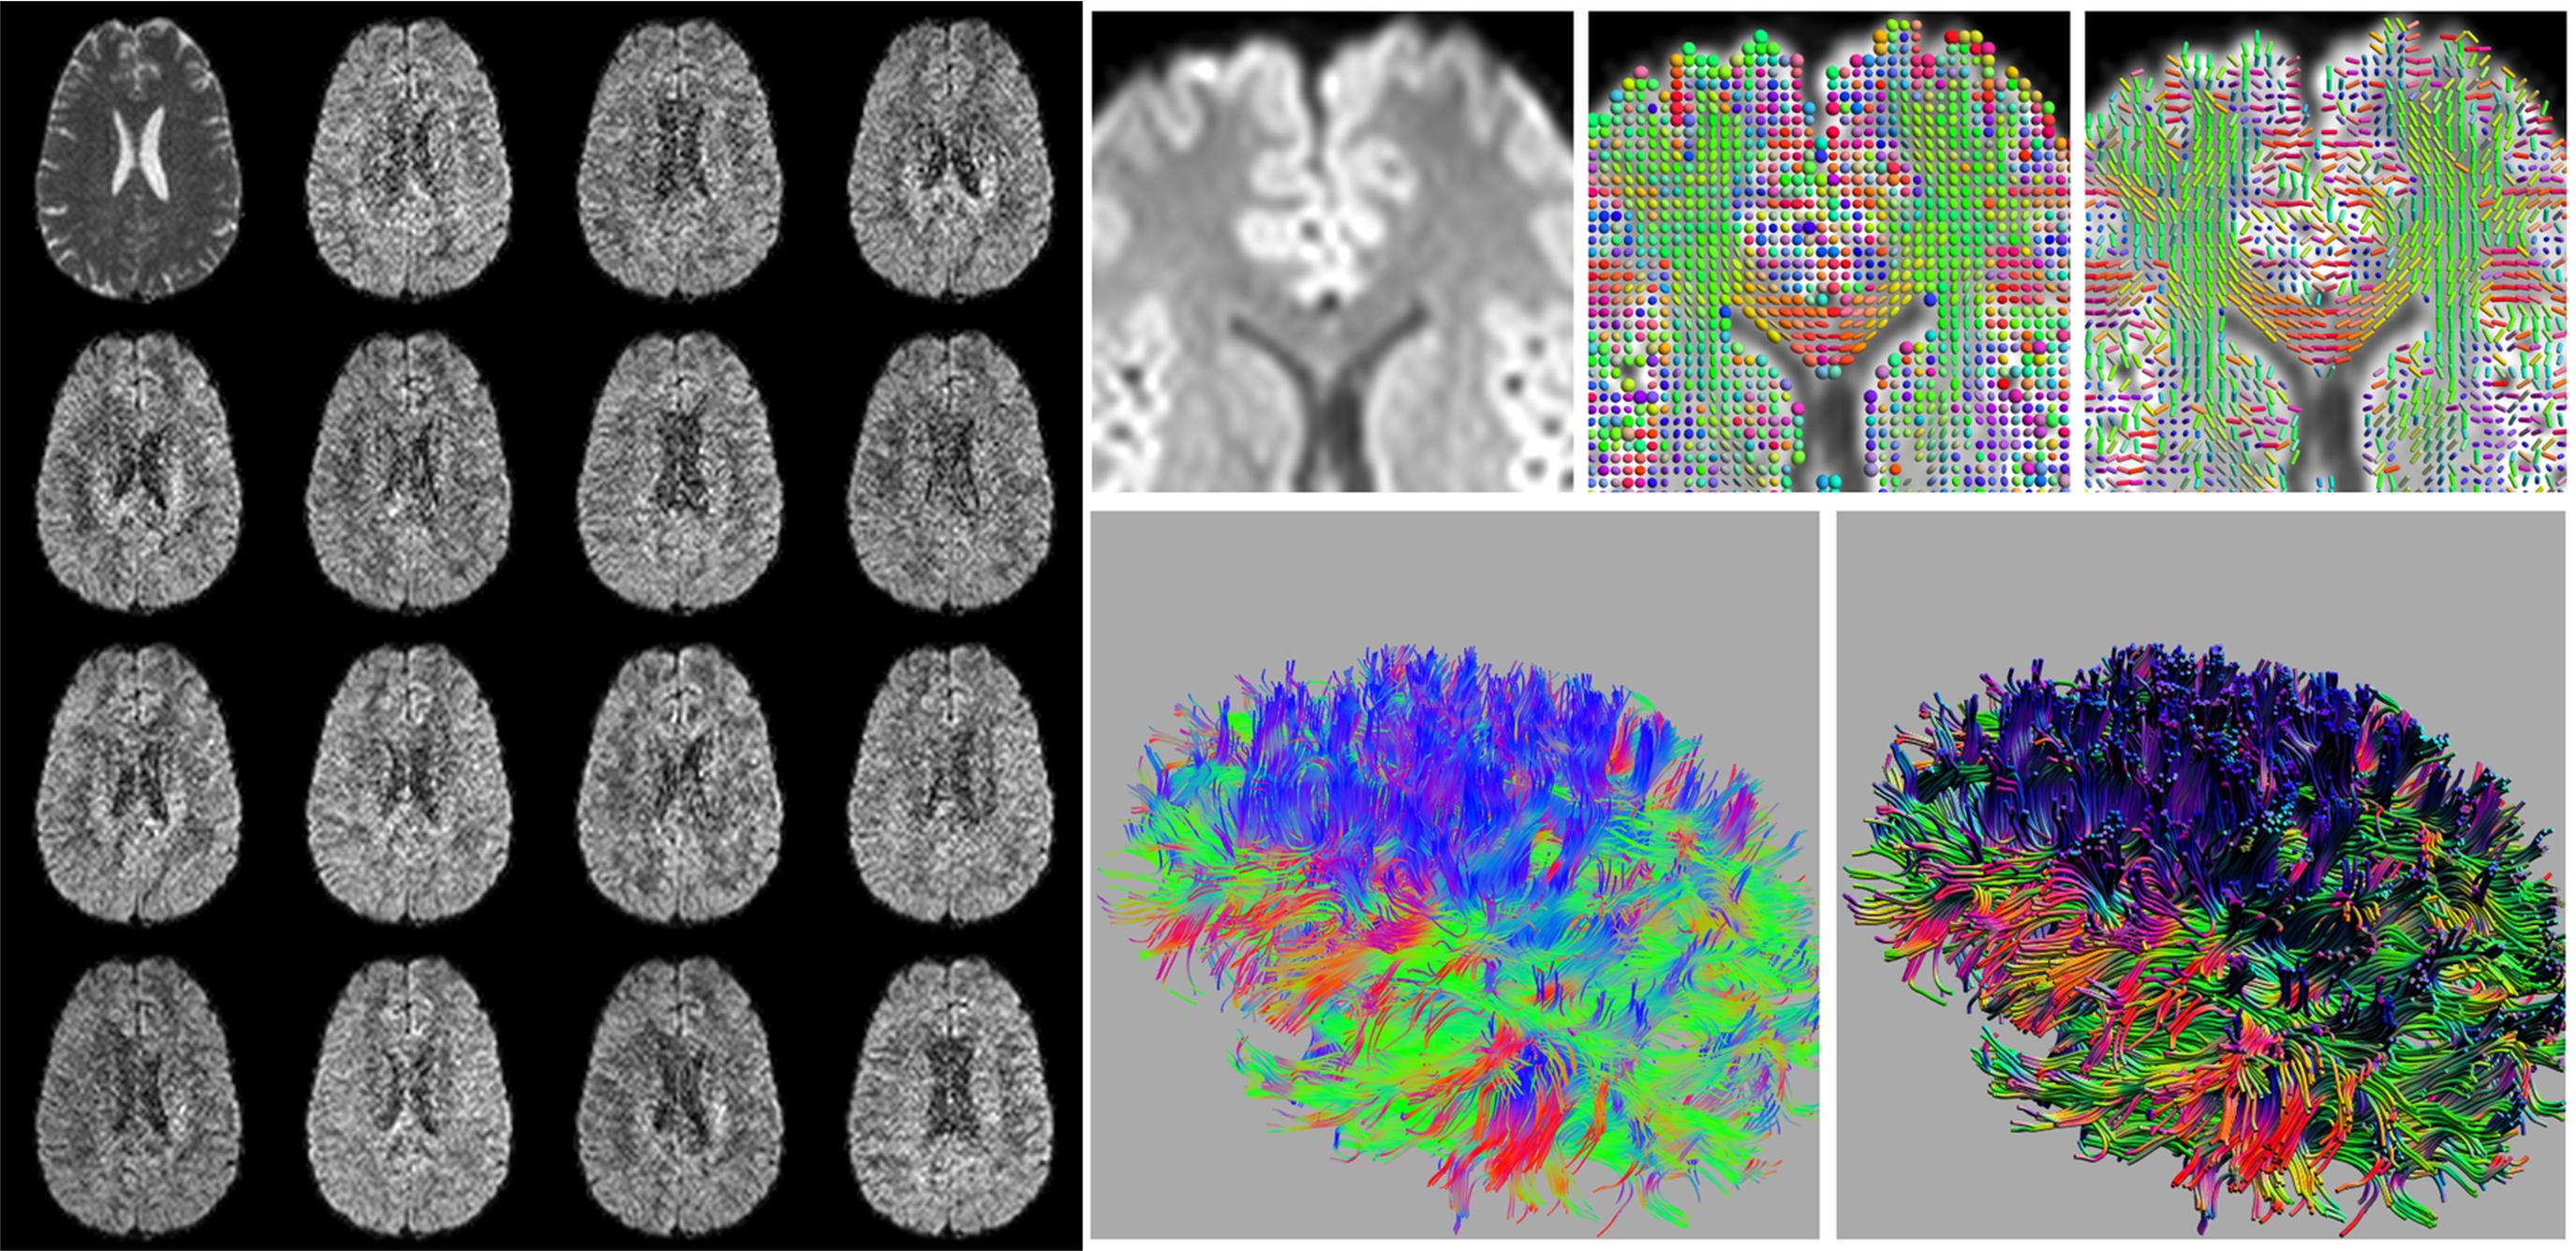

Diffusion tensor imaging based fiber tractography